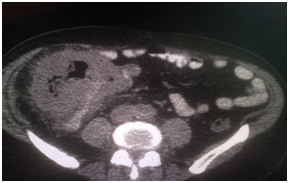

КТ брюшной полости от 21.03.16 – в слепой кишке объемное образование размерами до 98×118×108 мм, параколитическая клетчатка инфильтрирована, в окружающей клетчатке множественные лимфоузлы;

Выполнено ПЭТ/КТ исследование с 18F-ФДГ.

Выявлен гиперметаболический опухолевый процесс в области слепой и восходящей ободочной кишки (SUVmax 21,9), окружающая параколитическая клетчатка неравномерно инфильтрирована, с небольшим количеством жидкостного содержимого. Просвет кишки неравномерно сужен. В окружающей параколитической клетчатке, брыжейке тонкой кишки, отмечаются лимфоузлы,  размерами до 6-8 мм по КО, с умеренным накоплением РФП, SUVmax 4,3.

IMG_4389-27-09-18-09-40.JPG IMG_4389-27-09-18-09-40.JPG IMG_4389-27-09-18-09-40.JPG IMG_4389-27-09-18-09-40.JPG